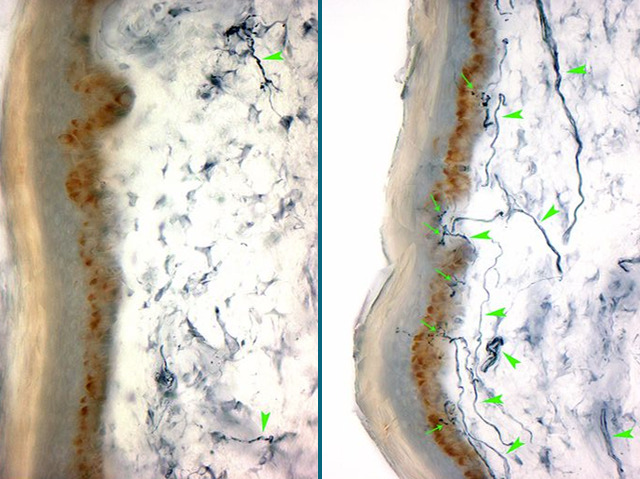

Our sense of pain is important for helping us to avoid injury, but imagine feeling pain without a cause. Patients with Sensory Peripheral Neuropathy suffer from tingling, numbness or burning pains, usually in their hands or feet. Symptoms occur when damaged sensory neurons [nerve cells] take incorrect pain messages from the skin to the brain. A skin tissue sample from a neuropathy patient (left) shows the almost complete loss of sensory nerve endings (indicated by green arrows), due to degeneration, in comparison with normal tissue on the right. The most common cause of nerve degeneration is diabetes but in around half of all neuropathy cases the cause is unknown. Current research is seeking causes of neurodegeneration in the hope of informing preventative measures and novel treatments for this debilitating condition.